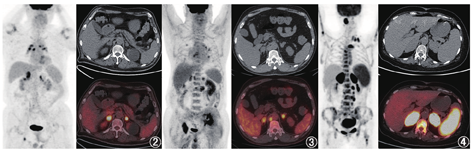

原发性肾上腺皮质功能减退可由自身免疫性疾病、感染性疾病(结核杆菌感染、真菌感染等)、转移瘤或淋巴瘤代替正常肾上腺组织、肾上腺出血/梗死或药物等原因引起[1,2],在我国最常见的原因为结核感染[3]。与结核感染相关的肾上腺皮质功能减退最常发生于老年男性。结核感染所致的肾上腺破坏通常呈渐进性,在病变早期,双侧肾上腺弥漫性增大,进展期形成低密度或软组织结节、肿块,密度均匀并代谢增高(图2),其病理组织学对应结核的上皮样细胞及多核巨细胞形成肉芽肿性炎,如果病灶内发生干酪样坏死,PET/CT显像则表现为肾上腺代谢增高区内伴局部代谢减低区,对应平扫/增强CT表现为低密度无强化区[4]。本例患者的影像学表现完全符合结核的特点及相应病理阶段,即炎性肉芽肿浸润的同时伴有中心干酪样坏死。肾上腺转移瘤可为单侧,也可为双侧,影像上通常表现为低密度或软组织密度结节、团块或肿块[5],代谢程度与原发灶程度相当(图3),转移瘤较大时病变中心会出现坏死。本例患者的PET/CT未发现全身其他部位原发肿瘤病灶,所以可除外肾上腺转移瘤。累及肾上腺的淋巴瘤多为侵袭性淋巴瘤,一般表现为肾上腺代谢明显增高的肿物(图4),病变一般比本例更大、代谢更高、囊变坏死更少[3,5],并且肾上腺外可见淋巴瘤病灶,所以本例暂不考虑淋巴瘤。另外,从肾上腺皮质功能减退的发生机制来看,由于肾上腺皮质具有很强的代偿能力,在出现肾上腺功能减退之前大多数的肾上腺皮质已被破坏。转移瘤和淋巴瘤都是肿瘤组织取代正常的肾上腺组织,只有当肿瘤较大、病变较晚期时才会出现肾上腺皮质功能减退;而结核等感染性病变对正常肾上腺组织的破坏力更强,更容易发生肾上腺皮质功能减退。所以从影像和临床综合来看,本例最有可能的诊断是肾上腺结核。